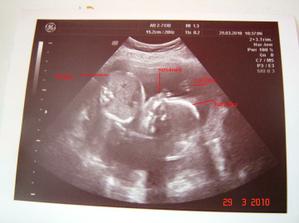

-12.4 velký UTZ potvrzeno je to holčička je v pořádku měří jak má ale zjištěno malo plodové vody a ztluštěna stěna placenty hematomního vzhledu (chjooo já snad nebudu mít klid do porodu) kontrolní velký ultrazvuk za 14 dní